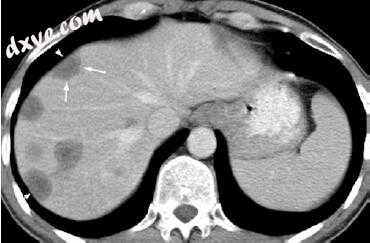

12.jpg

图17.12 HCC:用于检测和表征的四相CT。 (a)非造影CT显示肝硬化和脾肿大。在第4部分,病变只是微弱地看到。 (b)在动脉晚期,在第4段(箭头)中描绘了血管HCC。 (c)在静脉中

尽管不敏感(33%),但动脉期图像上的高密度与静脉或延迟期图像的清除与低密度相结合,对于HCC的诊断具有高度特异性(100%)(图17.11)。然而,与肝脏相比,一小部分HCC可以是异体血管或血管,这可能难以诊断。典型的MR成像特征 - 较大的HCC包括纤维囊/假包膜,瘤内隔,子宫结节和肿瘤血栓(图17.14)。这些病变在CT和MR上的外观(马赛克结构)通常是异质的。虽然大多数大的HCC在T2加权图像上是高信号,但是甚至3-4厘米的较小病变可能出现等信号或低信号。在T1加权图像上,HCC显示相对于肝实质的可变信号强度。肿瘤囊/假包膜可以在T1加权时观察到,并且不太常见,在T2加权成像时可以看作低信号。

HCC中的常规钆对比成像与针对CT描述的特征平行,具有特征性早期峰值对比度增强和结节性固体组分的延迟相位肿瘤对比度清除,以及囊/假包膜的晚期T1增强。肝脏特异性MR造影剂(钆喷酸或钆贝特图像,但边缘焦点显示更高的SI。(d,e)动态钆 - 增强T1加权GRE图像显示(d)恶性病灶的动脉血管过多(箭头)并且(e)在平衡期中洗出二葡甲胺)可以施用以提供动脉,门静脉和平衡相成像,但具有在对比增强的延迟肝胆相时显示出额外特征的附加优点。 HCC通常不显示肝胆相中肝脏特异性造影剂的对比度保留,这可以增加HCC检测和表征的可信度(图17.15)。已经表明,使用钆酸增强的MRI可以改善小或早期HCC的检测,因为与CT相比,它对于检测尺寸<1-2cm的HCC是优越的。此外,通过钆酸增强MRI检测到的亚厘米病变可能或可以在短时间内转变为HCC。因此,HCC成像评估的几个不断发展的指南正在纳入肝脏特异性造影剂在诊断亚厘米HCC中的作用。亚临床HCC可以通过局部治疗来治疗,从而避免与根治性手术相关的发病率和死亡率。

13.jpg

图17.13具有结节状结节的HCC。 (a)未增强的CT显示出大量结节(高度衰竭)的大结节,其中包含低密度(非侧脑室)焦点(箭头)。 (b)在T1加权的GRE反相图像上,边缘结节显示低信号强度(箭头)。 (c)大结节显示T2加权TSE的萎缩